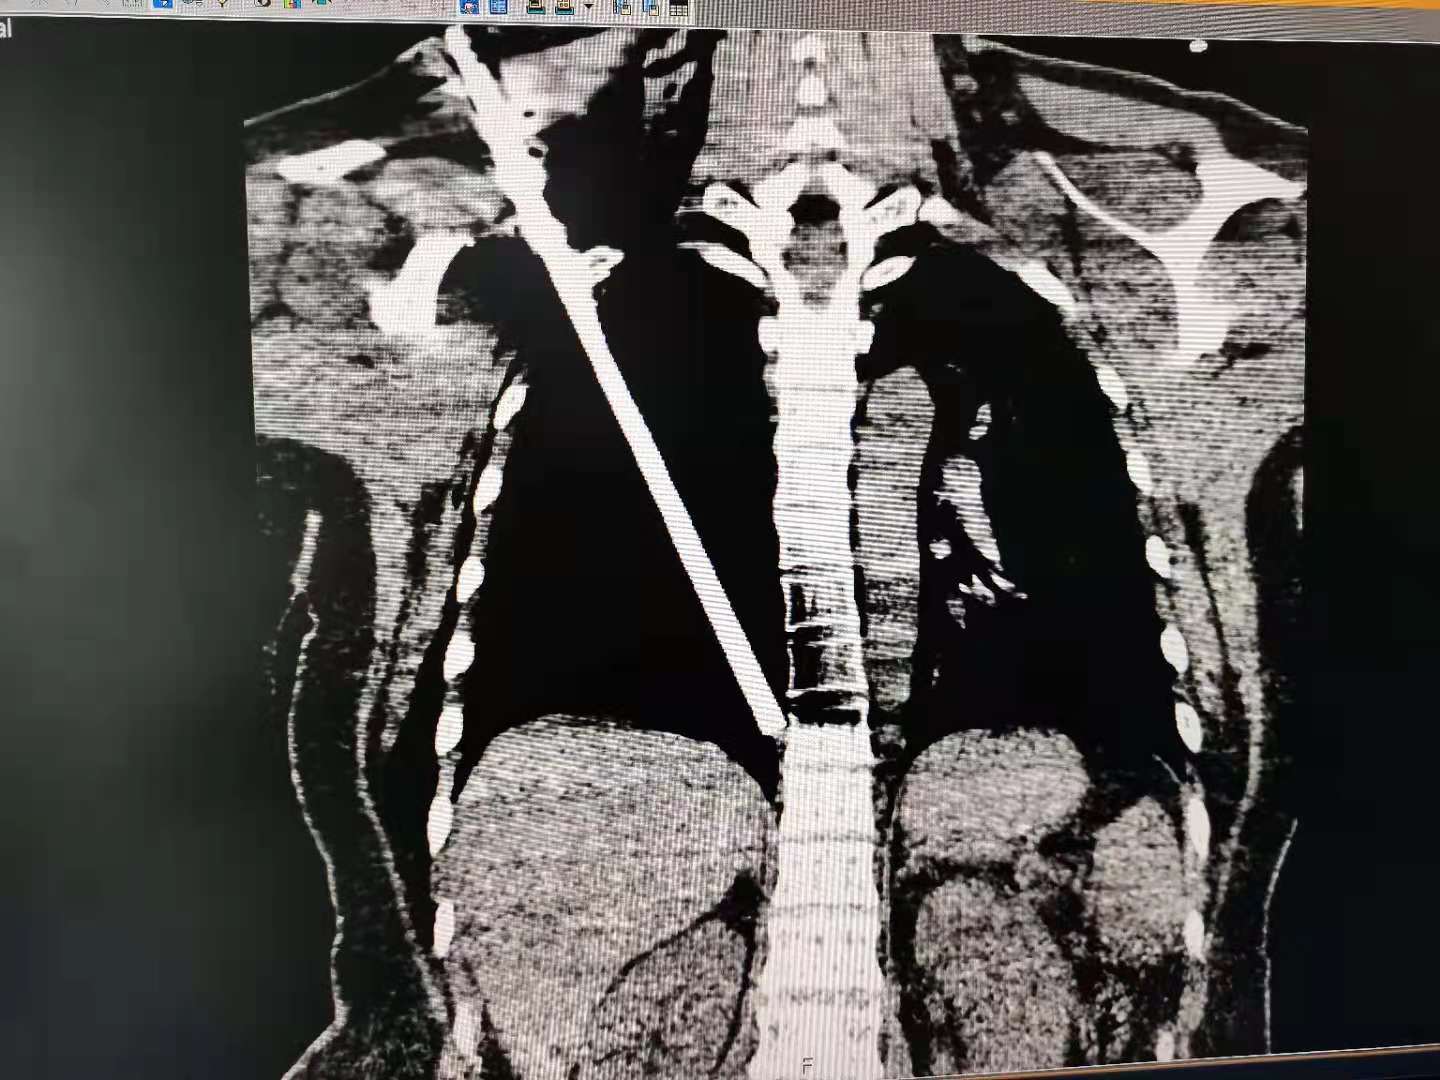

近日,桂林某工地上演惊魂一幕!32岁的金某在工地干活,突然一根长达6米的钢筋从天而降,金某躲闪不及只见这钢筋自其右肩入,腹腔出,整根钢筋穿胸而过……

钢筋穿胸而过距离心脏仅1.5cm

伴随着119和120的警笛“救援”二重奏,金某被送进了自治区南溪山医院急诊科,该院急诊科的医护人员立即进行了应急处理并开通了绿色通道,经过一系列必要的检查,发现钢筋造成了金某肺部的严重损伤,随即金某被推进了手术室,自治区南溪山医院胸外科副主任许可团队避开金某胸腔内的各种复杂动脉血管和脏器直取钢筋,仅用1小时40分就成功将这穿膛而过钢筋顺利取出。目前金某已经拔管,生命体征平稳,正在该院胸外科进行恢复治疗。

长达35cm钢筋被取出体外